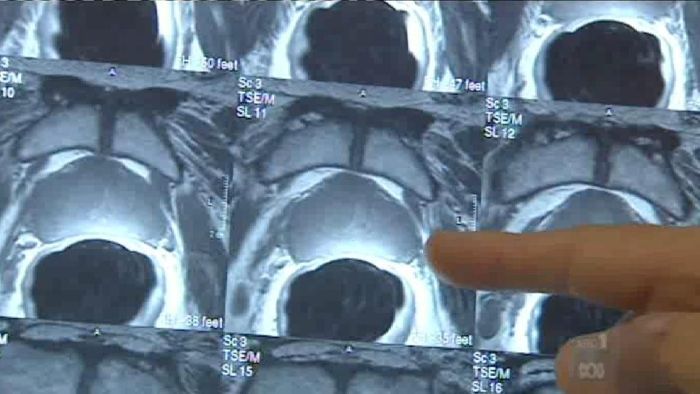

A bank of biopsies maintained for 20 years at Garvan and St Vincent’s Hospital, allowed the analysis of samples from 185 men who had their prostate removed due to a cancer diagnosis in the 1990s and 2000s.

They examined their genomes and identified 1420 regions specific to the prostate cancer where they could see epigenetic changes – marks on the DNA known as methylation.